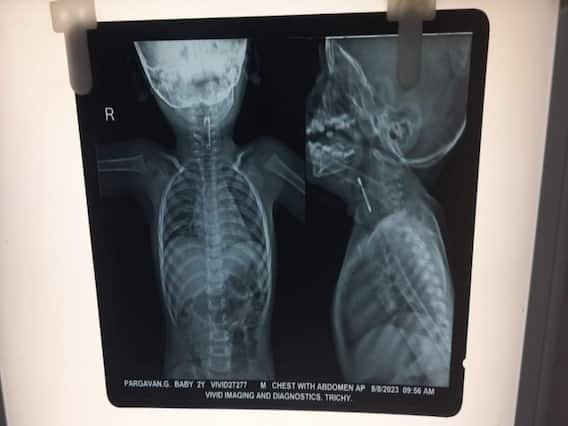

ஊக்கை விழுங்கிய குழந்தை:

இந்நிலையில் திருச்சி புதுக்கோட்டை நெடுஞ்சாலையில்  விமான நிலையம் அருகில் உள்ள குண்டூர் பர்மா காலனியை சேர்ந்த இரண்டு வயது குழந்தை உணவு உட்கொள்ளும் போது தவறுதலாக ஊக்கை முழுங்கியது. இதனால்  குழந்தை மூச்சு விட சிரமப்பட்டதை அடுத்து என்ன காரணம் என்று தெரியாத பெற்றவர்கள் திருச்சி மகாத்மா காந்தி நினைவு அரசு மருத்துவனைக்கு சிகிச்சைக்காக கொண்டு வந்திருந்தனர். திருச்சி அரசு தலைமை மருத்துவமனையில் உள்ள குழந்தைகள் சிகிச்சை பிரிவில் குழந்தையை எக்ஸ்ரே எடுத்து பார்த்த போது தொண்டை பகுதியில் ஊக்கு இருப்பதனை மருத்துவர்கள் கண்டுபிடித்தனர்.

இதனை அடுத்து திருச்சி மகாத்மா காந்தி நினைவு அரசு மருத்துவமனையில்  உள்ள காது மூக்கு தொண்டை துறையின் தலைமை மருத்துவர் அண்ணாமலை தலைமையிலான மருத்துவ குழுவினர் உடனடியாக குழந்தைக்கு மயக்கம் மருந்து கொடுக்கப்பட்டு டியூப் வாயிலாக ஊக்கை வெளியே எடுத்தனர். இந்த நிலையில் தற்போது குழந்தை நல்ல ஆரோக்கியத்தோடு வீட்டிற்கு அனுப்பி வைக்கப்பட்டுள்ளது.